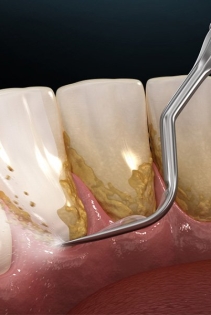

Bao lâu nên cạo vôi răng? Tìm hiểu tần suất lấy cao răng chuẩn giúp ngăn ngừa hôi miệng, viêm nướu và bảo vệ răng miệng hiệu quả.

Vôi răng là mảng bám cứng đầu gây hôi miệng, viêm nướu và mất thẩm mỹ. Tìm hiểu nguyên nhân, cách phòng ngừa và quy trình cạo vôi răng nhẹ nhàng, không đau tại Nha khoa SV – Quận 3.

Cạo vôi răng định kỳ giúp phòng ngừa viêm nướu, hôi miệng và giữ răng chắc khỏe. Tìm hiểu quy trình, lợi ích và chi phí cạo vôi răng tại Nha khoa SV – nha khoa uy tín Quận 3.

Tụt nướu (tụt lợi) gây lộ chân răng, ê buốt, mất thẩm mỹ và nguy cơ mất răng. Tìm hiểu nguyên nhân, phương pháp điều trị tụt nướu – viêm nha chu và bảng giá chi tiết tại Nha Khoa SV.

Viêm nha chu là bệnh lý răng miệng nguy hiểm có thể gây mất răng nếu không điều trị kịp thời. Tìm hiểu nguyên nhân, dấu hiệu và phương pháp điều trị viêm nha chu hiệu quả tại Nha Khoa SV.